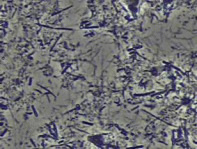

当院では、「ジスロマック」と呼ばれる抗菌薬を用いて歯周病菌の殺菌を行っています。下記の画像は、治療前と治療後の口腔内を特殊な顕微鏡で撮影し比較したものです。投薬後には歯周病菌の数が大幅に減少していることが確認できます。

従来の機械的な歯石除去だけでは除去しきれない深部の汚れや、歯周ポケット内の細菌叢(フローラ)をコントロールするために、薬剤との相乗効果が期待できます。この治療法は、外科手術を回避できる場合があるなどのメリットがある一方で、患者さん個々の歯周ポケットの深さや歯肉の状態によっては適応が限られるケースもあります。

そのため、当院では診断結果を踏まえて最適な治療手段を提案し、痛みやダウンタイムを最小限に抑えながら症状の改善を図っています。薬剤を用いた局所的な殺菌アプローチと組み合わせることで、再発率を下げ、治療効果の持続を目指しています。